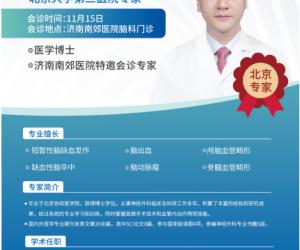

- 12-18北医三院脑科专家尹晓亮博士12月20日莅临南郊医院 疑难脑病会诊再启

- 12-11脑血管病患者福音!北大三院尹晓亮博士12月13日莅临济南南郊医院开展专家会诊

- 11-14好消息!北京脑科专家尹晓亮博士来济南南郊医院会诊啦!

- 11-11北医三院脑科专家尹晓亮博士加盟济南南郊医院 齐鲁百姓家门口享顶尖诊疗

- 11-08重磅官宣!北医三院尹晓亮博士加盟济南南郊医院守护脑健康

- 11-06北医三院脑科专家尹晓亮博士加盟南郊医院守护泉城百姓“脑健康”

- 12-18北医三院脑科专家尹晓亮博

- 12-11脑血管病患者福音!北大三